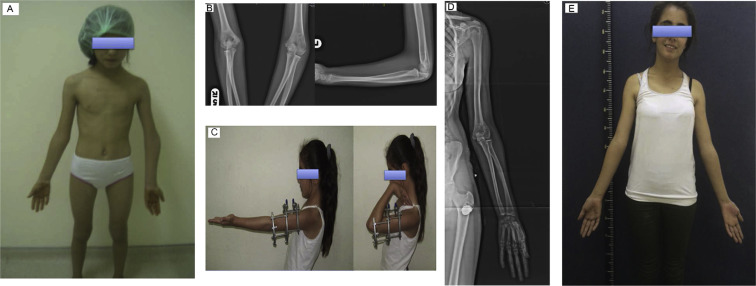

Regarding complications, there were 2 grade 1 pin tract infections treated with appropriate dressing and oral antibiotic, and 1 diaphyseal fracture of humerus at proximal Schanz screw insertion caused by forceful manipulation during physiotherapy after removal of fixator. Circular external fixator was reapplied until solid union of fracture was achieved. No neurovascular complications occurred. Functional outcome was rated excellent in 7 patients, and good in 1 patient. Clinical and radiographic views of 2 patients each treated for cubitus varus and valgus deformity are provided in Fig. 2 ; Fig. 3 , respectively.

|

Fig. 2. Ten-year-old girl with cubitus varus (patient #2). (a) Clinical appearance. (b) Anteroposterior and lateral radiographs before correction. (c) Flexion and extension after correction. (d) Anteroposterior radiograph at last follow-up. (e) Clinical appearance at last follow-up. |